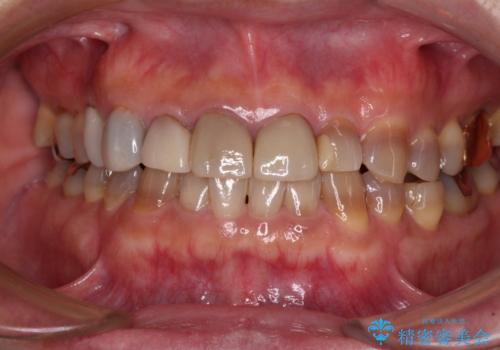

- 前歯のテトラサイクリンによる変色歯と、レジン充填の色の違いを気にして来院された患者様です。

患者様の希望により、前歯6歯をオールセラミッククラウンにて補綴することとしました。

長年前歯の色の違いに悩んでいらっしゃったようですが、仮歯に変えた時点で統一感のある白さとなり喜んで頂きました。

わずか1ヶ月の間にとても自然な仕上がりのセラミッククラウンが装着され、患者様には大変満足していただきました。